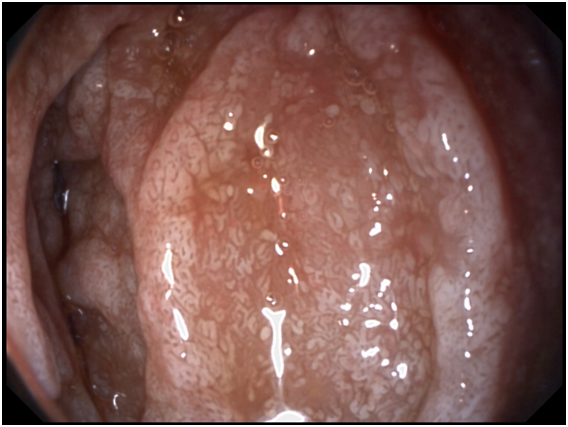

A 53- years old male presenting with chronic diarrhea of 8months duration, his diarrhea was of large volume, frothy in nature with foul odour. It was not related to a specific type of food, persisted during fasting with no diurnal variations. His condition was also associated with significant weight loss. The condition was associated with low grade fever and arthralgia of his both knee and hip joints. After 2months from the onset of his diarrhea he started to develop dizziness and easy fatigability. Physical examination of the patient was unremarkable apart from the pallor. Work up for diagnosing the cause of his diarrhea was done in the form of repeated stool analysis and culture, complete blood count, liver profile, renal profile, electrolytes, ESR, B2 microglobulins, virology (HIV, HBsAg, antiHCVab) and thyroid profile. All the previously mentioned investigations were normal apart from microcytic hypochromic anemia due to iron deficiency with haemoglobin=7.3mg/dl, serum Fe was 10mg/dl and transferrin saturation was 5%, also he had mild hypoproteinemia with serum total protein of 6.2g/dl and mild hypoalbuminemia with serum albumin of 3g/dl. His ESR was 123 and C-reactive protein (CRP) was 49mg/dl as shown in Table 1. Abdominal ultrasound was completely normal. Attempts of giving empirical medications in the form of metronidazole and quinolones failed to control the condition of the patient. Endoscopic intervention was decided in the form of upper endoscopy and colonoscopy. Total colonoscopy and terminal ileoscopy were done with no abnormality detected. For the upper endoscopy; the duodenal mucosa down to the proximal jejunum was markedly congested with extensive whitish mucosal patches as shown in Figure 1-3. Multiple biopsies were taken; histopathological examination showed focal villous distortion and focal villous erosions. The lamina propria showed mild mono-nuclear cell infiltrate with extensive infiltrate of foamy macrophages with dilated lymphatic spaces as shown in Figure 4. PAS (periodic acid shiff) stain was applied during microscopic examination where the organism was detected as shown in Figure 5. And hence the patient was diagnosed as a case of Whipple’s disease (WD). Then treatment was started accordingly in the form of ceftriaxone for 15days followed by trimethoprim-sulfamethoxazole (TMP/SMX) twice a day for 1 to 2years with marked improvement of the patient's condition. The improvement was evident by his laboratory parameters (Table 1) and endoscopic picture (Figure 6).

Figure 3 Endoscopic view of Whipple's disease.

Diagnosis is made from duodenal biopsy, taken by upper endoscopy, which reveals pale yellow shaggy mucosa with erythematous eroded patches in patients with classic intestinal Whipple's disease25 and this is seen in our patient. Histopathological examination of the duodenal biopsies shows infiltration of the lamina propria with PAS-positive macrophages with intracellular clumps of T. whipplei.3 Immunohistochemical staining for antibodies against T. whipplei has been used to detect the organism in a variety of tissues, and a PCR-based assay is also available.26 Electron microscopy can be diagnostic showing coccobacillary bodies that represent the T. whippeli organism. Histologic examination with routine H&E and PAS stains is usually sufficient to reach a diagnosis, however, it is recommended that PAS-positive histologic findings to be confirmed with other methods when establishing the diagnosis of WD.25,26